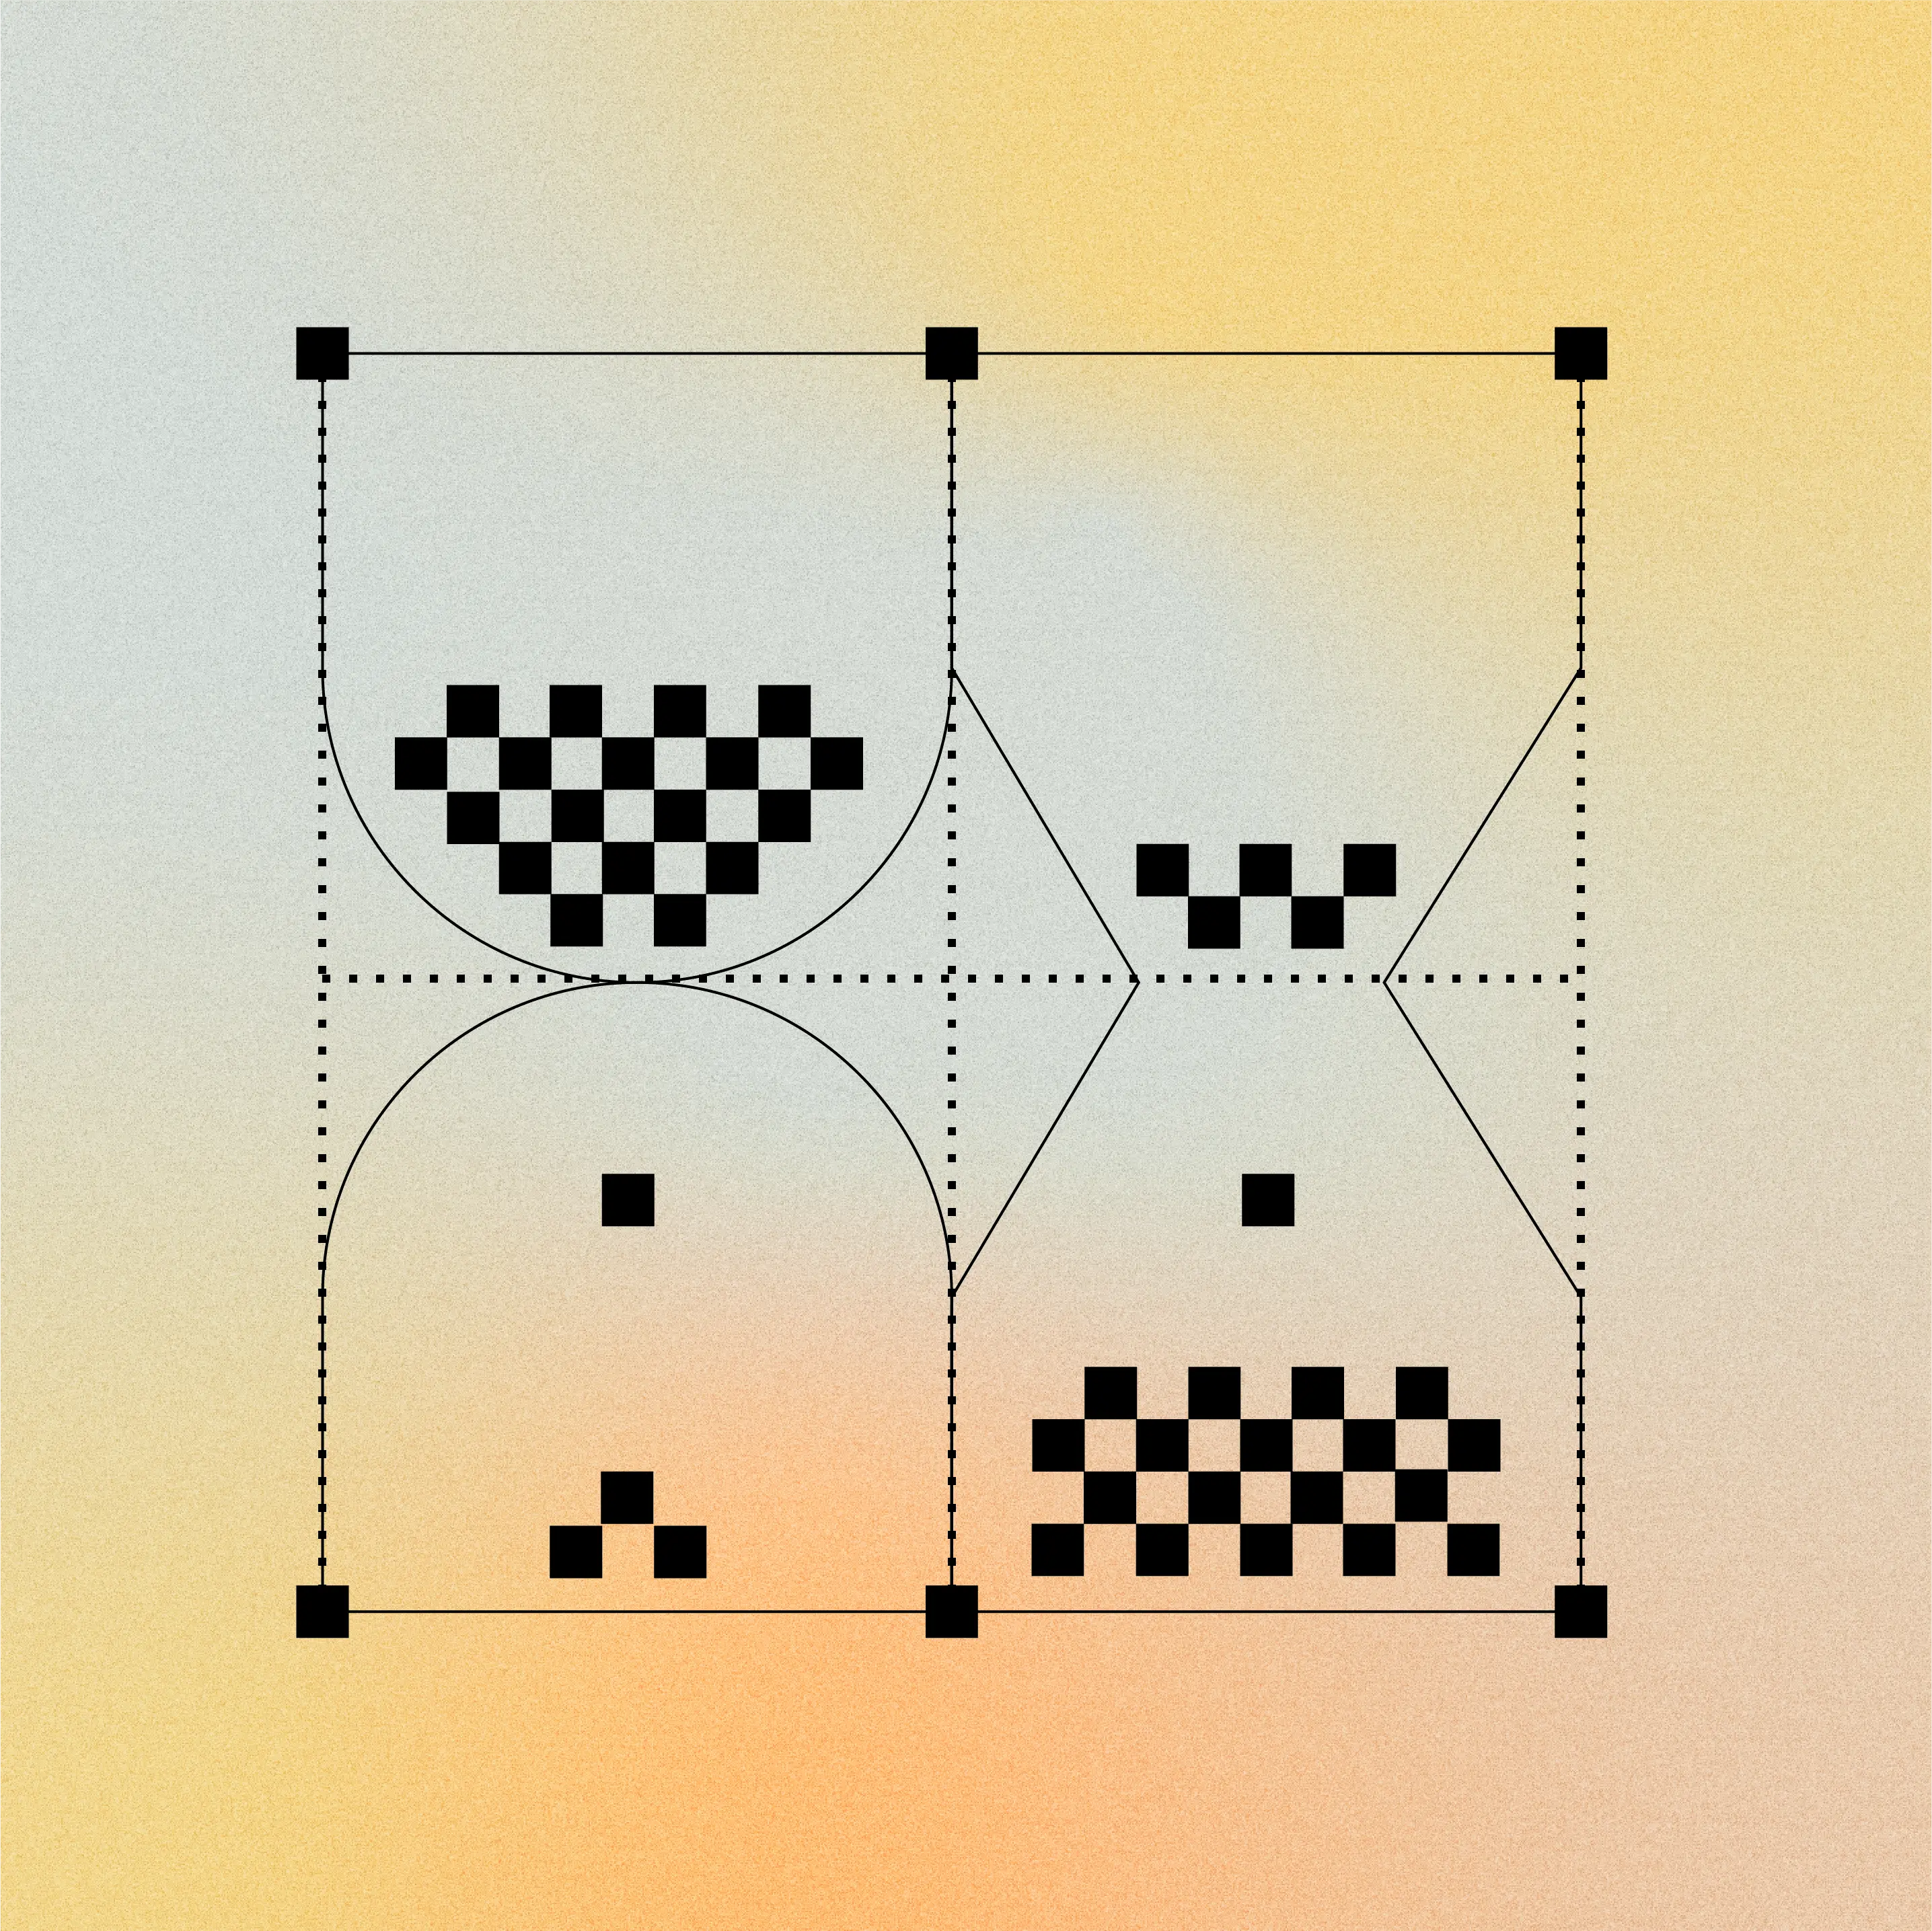

We generate development candidates that combine numerous differentiating properties

Bespoke

Pharmacology

Enhanced affinity, exquisitely selective target binding, and no non-specific tissue binding to enable a mechanism of action with maximized potency and safety.

Tailored

Pharmacokinetics (PK)

PK precisely tailored to maximize safety, efficacy, and convenience

For solid tumor delivery: persistent tumor exposure, with rapid clearance from healthy tissues (plasma half-life of hours to days)

For non-oncology indications: long-acting PK to increase drug exposure and reduce dosing frequency (plasma half-life of months)

Optimized

Developability

Manufacturing consistency and convenient, high-dose subcutaneous formulations